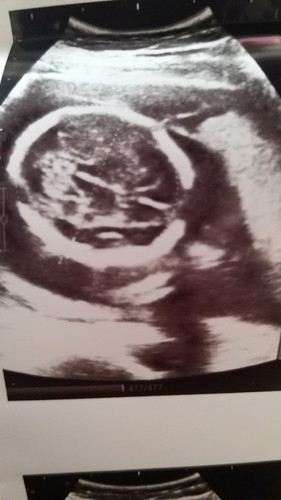

คุณหมอที่โรงพยาบาลซาวให้ บอกว่าน่าจะผู้หญิงค่ะ ยังไม่ชัว อยากรู้เค้าดูตรงไหนคะ พอดูออกมั้ยคะ

ภาพที่ซาวได้มาไม่ใช่ตรงเพศน้องค่ะ ถ้าจะดูเพศจะเป็นช่วงหว่างขาน้องค่ะแม่ ถ้าเห็นชัดๆก็บอกเพศได้ค่ะถ้ายิ่งน้องผู้ชายก็ดูได้ไม่ยากเลยค่ะ

ในรุปนี้เป็นสมองคะหรือส่วนหัว ไม่สามารถดูเพศได้

ผมที่ซาวด์เป็นหัวน่ะค่ะ